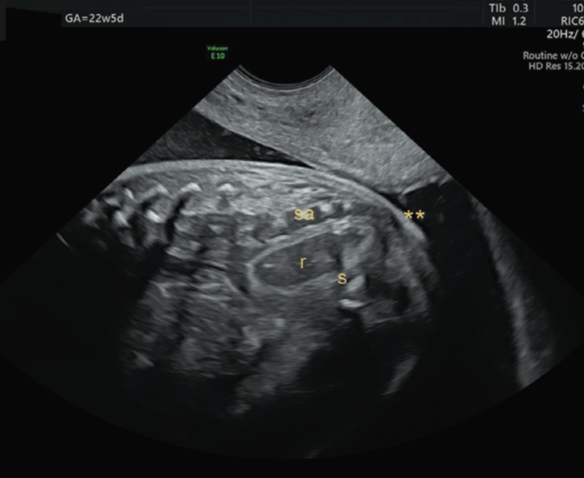

•  Mặt cắt dọc qua của sổ tầng sinh môn hoặc dưới xương cùng(infracoccygeal / transperineal) (3)

• Ưu điểm:

• Thấy toàn bộ ống hậu môn – trực tràng

• Phát hiện sớm (từ ~14 tuần)

• phân biệt:ARM cao (ARM thấp #65% và ARM cao-trung gian# 35%)

• Nhược điểm:

• Mới, chưa phổ biến

• Chỉ được chứng minh trong nhóm nguy cơ cao

• Có thể hạn chế ở thai lớn do lúc này xương cùng bị vôi hoá

Hình 6: khảo sát hâu môn trực tràng bằng phương pháp cắt dọc. Nguồn: Elkan Miller (2024)